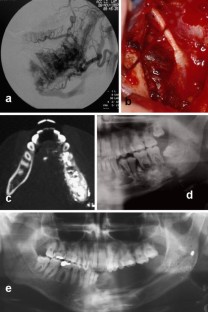

Arteriovenous malformation (AVM) of the mandible is not only a rare entity, but also one that can be potentially life threatening due to massive haemorrhage. The authors describe three cases of children with AVM of the mandible.

Sakkas, N., Schramm, A., Metzger, M.C. et al. Arteriovenous malformation of the mandible: a life-threatening situation. Ann Hematol 86, 409–413 (2007). https://doi.org/10.1007/s00277-007-0261-2